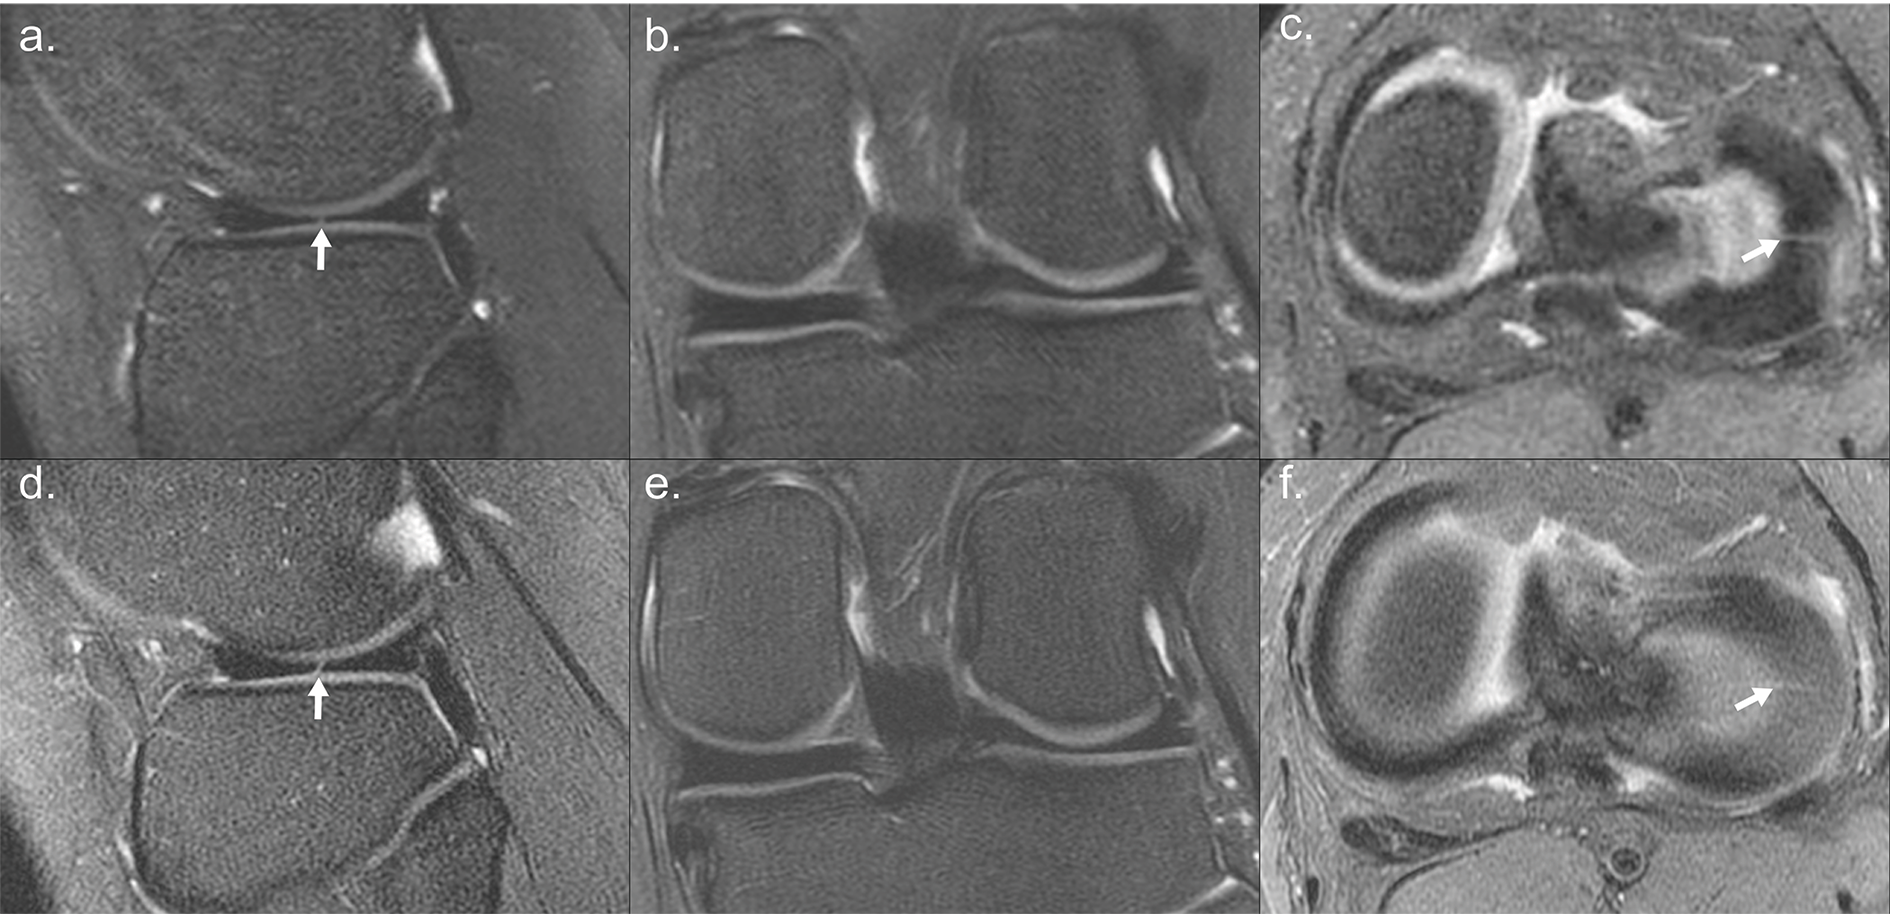

A prior study with 30 patients investigating a single sequence protocol using T2sh, compared against a conventional lengthy protocol, indicated that missing clinically relevant pathology is unlikely$$$^2$$$. A representative comparison between T2sh and conventional 2D MRI from the is presented in Figure 3. As additional patients can now be accommodated into the MRI schedule, the cost of the MRI is simply professional costs of the radiologist and minimal costs associated with reporting infrastructure. The magnet, technologists, and receptionists are already present. A significant additional benefit is same-day scheduling, which reduces lost productivity of parents and children at their work and school.

Representative case from prior study comparing T2sh to conventional 2D MRI. 16-year-old girl with a radial tear of the lateral meniscus. (a-c) T2Sh T2W sagittal, intermediate coronal reformatted, and PD axial reformatted images with similar delineation of anatomic structures compared to (d-f) 2D FSE FS T2W sagittal, FS T2W coronal, and FS PD axial images. The radial tear of the lateral meniscus (arrows) is well visualized on the T2Sh PD axial reformatted image (c).